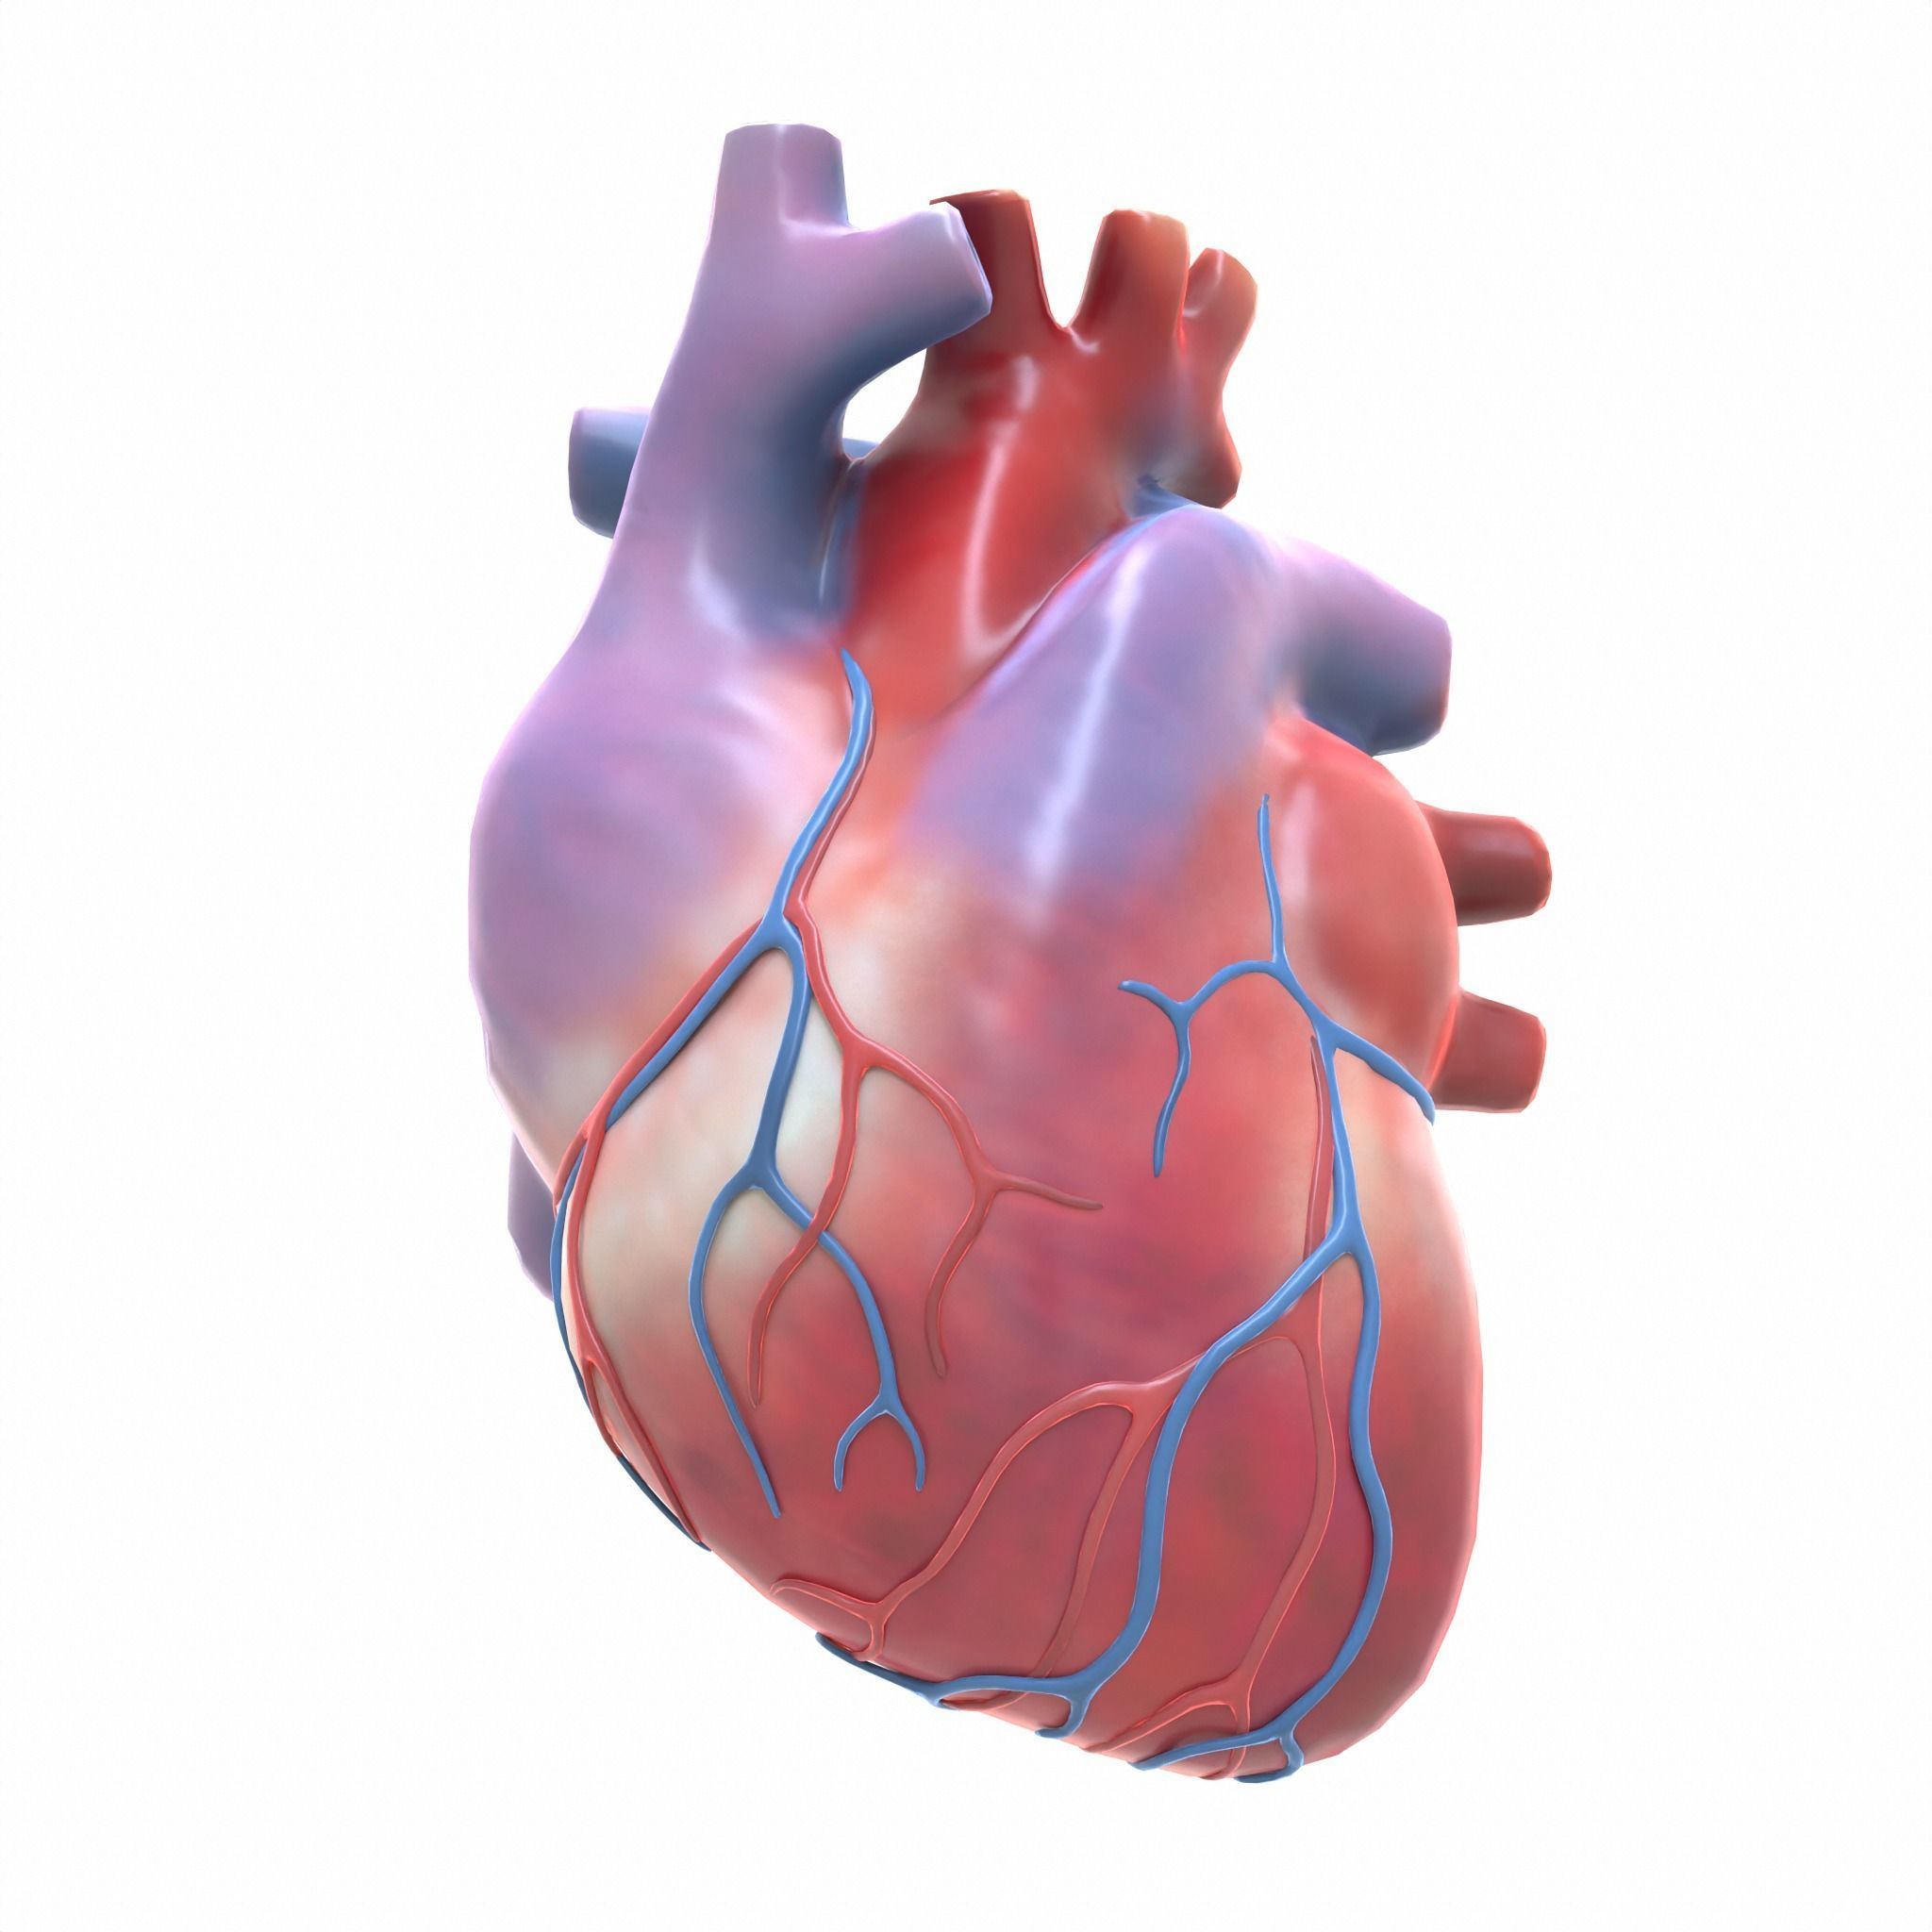

Health Care: Human Heart Anatomy Pics  Gross Anatomy Of The Human Heart Digital Art by Stocktrek Images

Gross Anatomy Of The Human Heart Digital Art by Stocktrek Images  Human Heart Drawing by Granger - Fine Art America

Anterior view of human heart anatomy Poster Print by Photon Illustration/Stocktrek Images  Cartoon Anatomical Heart

Human Heart Images Real - img-extra  //thebrainstormlab.com/banners/ami_banner.jpgThis is a medical | Heart anatomy drawing, Human

Human Heart 3D model realtime | CGTrader  Heart - Human Anatomy - PDF Zentangle Coloring Page | Human heart drawing, Human heart art